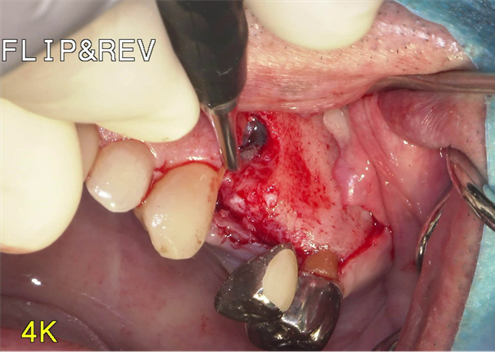

①歯根破折により右上小臼歯が動揺し、歯肉が腫れてしまい、周囲の歯槽骨が吸収していてインプラント埋入

が出来ないと他院で診断され、当院にインプラント治療を希望されました。

①歯槽頂よりサイナス

リフトを行いました。

②血液成分とカルシウム材料により骨造成をしました。